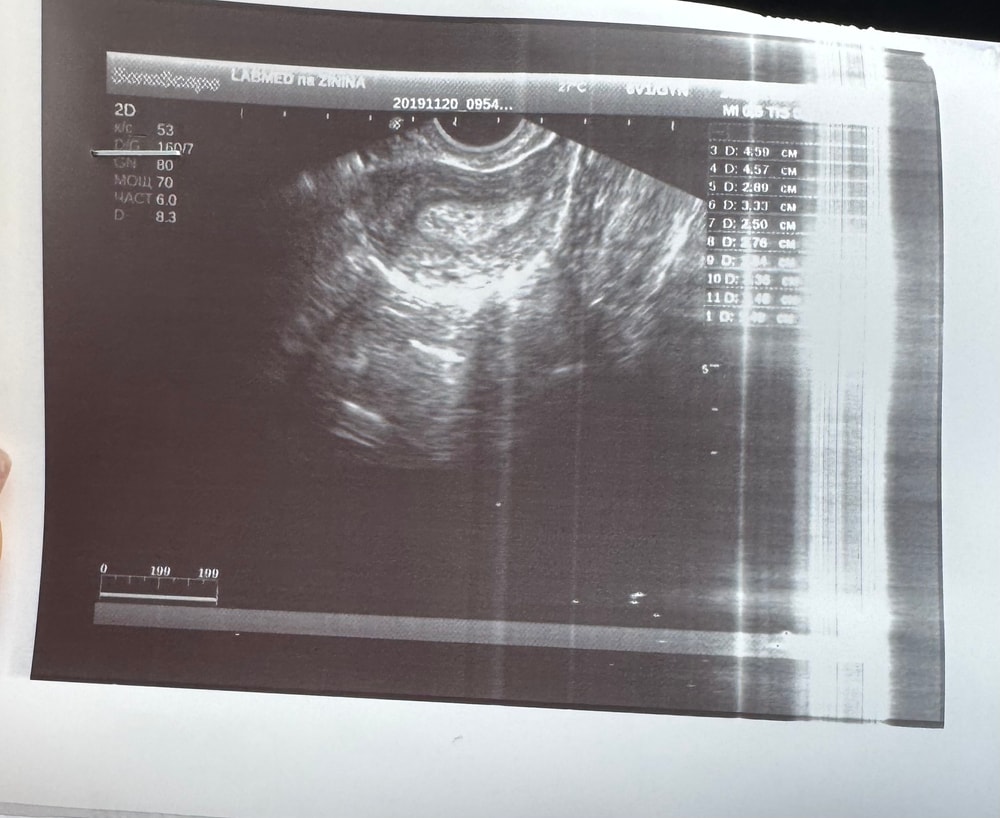

УЗИВот и прошли 8 дней. Сходила на узи, пока ничего не понятно, но очень ждём роста⤵️

врач в матке видит мааааленькое черненькое пятнышко, но пока утверждать ничего не может.

В прошлом посте писала о том, что был обнаружен второй доминантый фолликул, поздравьте, он тоже лопнул. В ЛЯ 2 желтых тельца. Но, сейчас посмотрела заключение, что-то меня смущает, что первое тело уменьшилось, это норм? Может потому, что их теперь два или размеры варьируются в зависимости от того, как датчиком водят? Не спросила, рассматривать начинаю только в машине🫠🫠🫠

В комментариях прикрепила заключение узи.